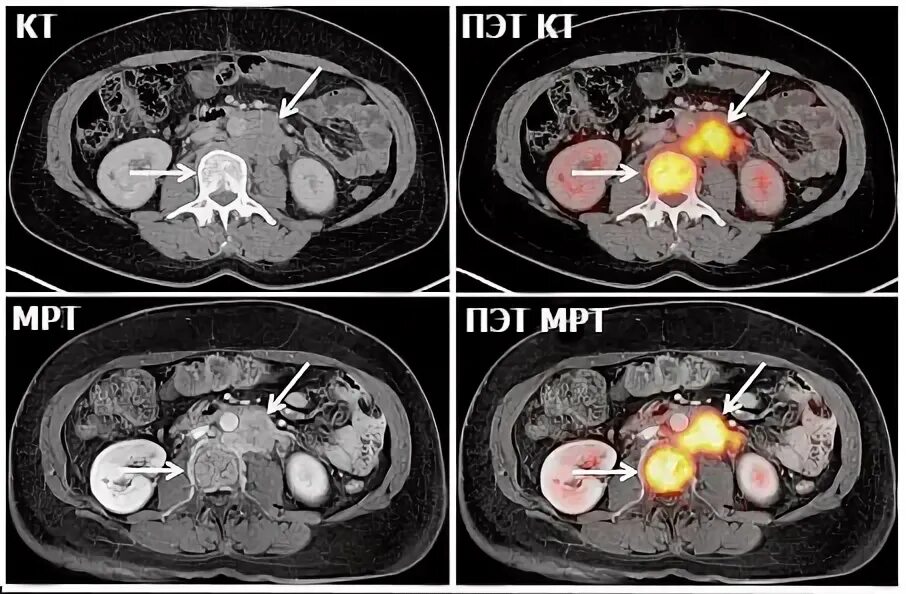

Кт и мрт